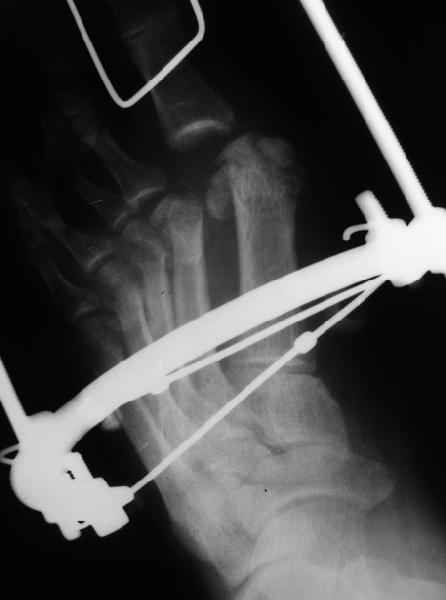

Они же наложили дистракционный аппарат (вместо того, чтоб сделать открытое вправление зафиксировать это одной спицой Киршнера), продержали больного две недели в аппарате (ЗАЧЕМ?), а теперь спрашивают , что делать...

продержали больного две недели в аппарате (ЗАЧЕМ?), а теперь

Да вроде ни про какие 2 недели там не было. Так все-таки, что бы Вы сделали именно сейчас у данного пациента, окажись он внезапно с этим аппаратом в Вашем ведении?

Имеем - без малого двухмесячные переломовывихи перeднего отдела стопы , больной в отделении 20 дней, доктор думает, что ему делать:

1 Спасибо за подробное объяснение - я действительно не понял, что , рассказывая про Вейля, имелся в виду второй палец. В принципе, я очень ( может быть, чрезмерно) расстроен ситуацией , когда больной находится в крупной (областной? Краевой? ) больнице 3 недели с невправленным вывихом пальца стопы, а его врач в интернете советы собирает. Кстати, судя по ответу <По поводу остеотомии Вейля - в ДАННОМ случае мы уже создали запас тканей дистракционным аппаратом.> - доктор глухов понял Вас так точно, как и я.